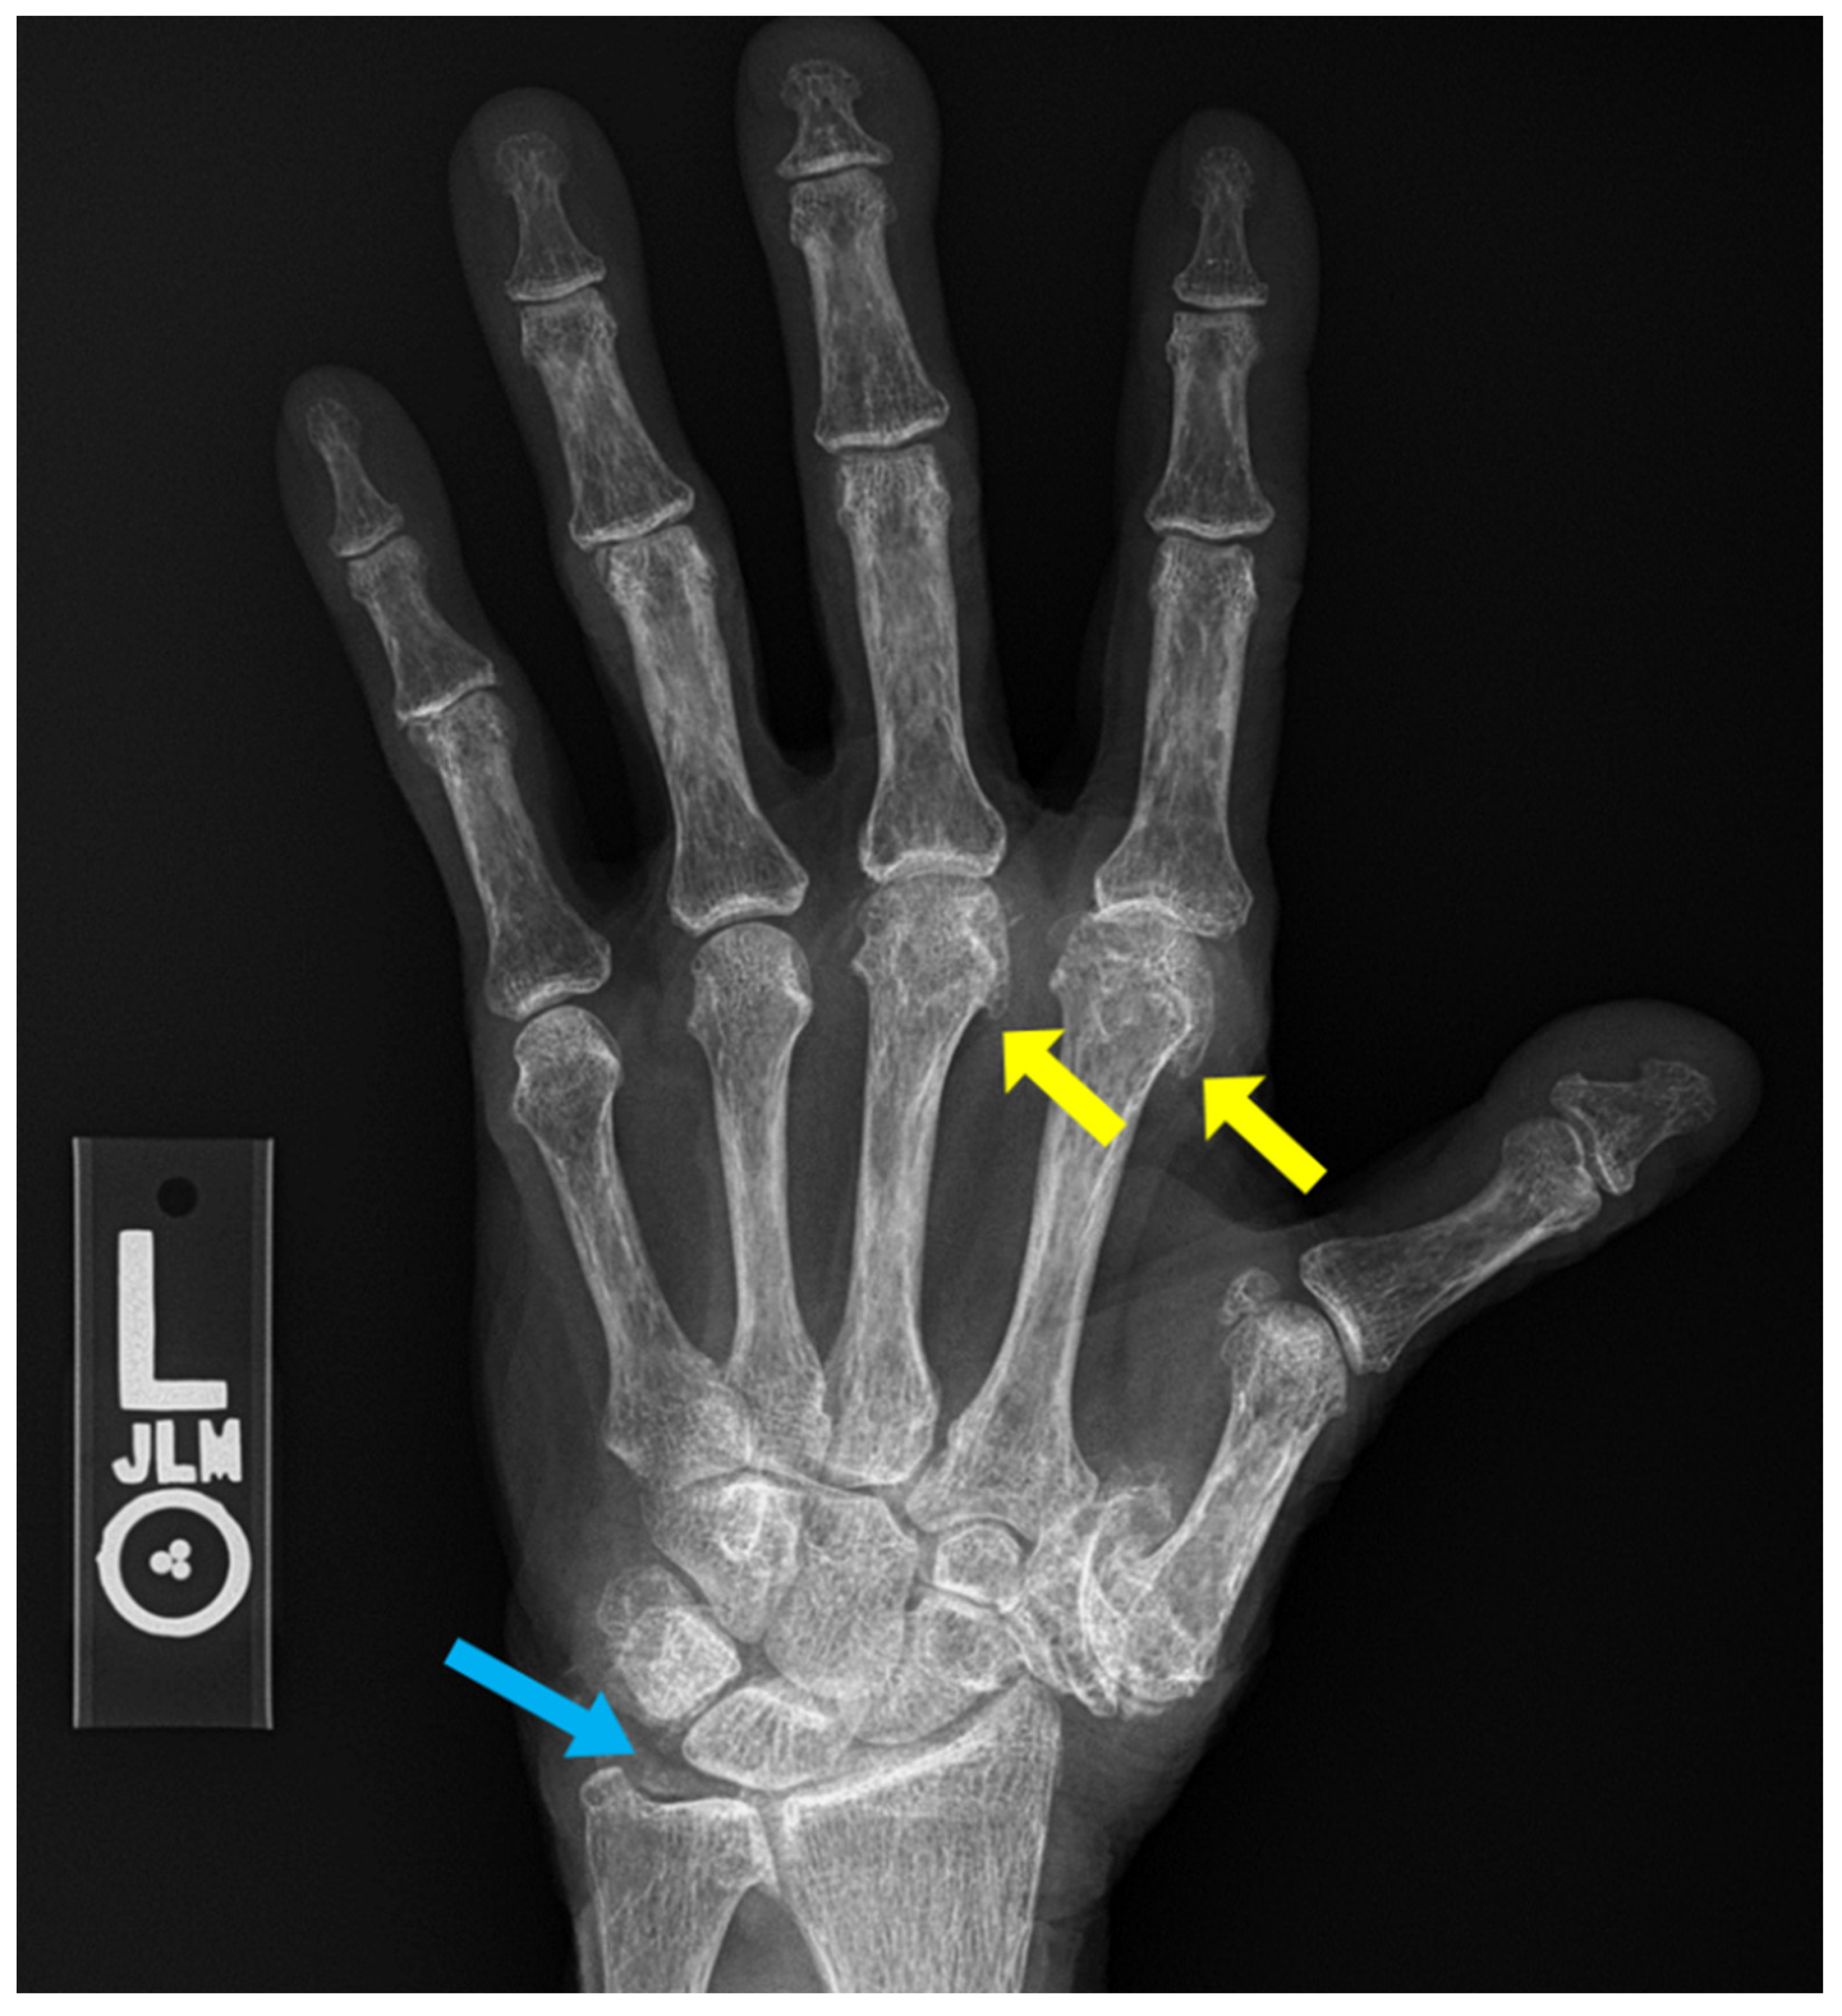

7. Calcium Pyrophosphate Dehydrate Arthropathy (CPPD)